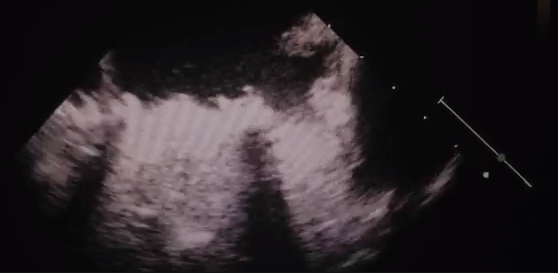

Her past surgical history was notable for three prior valve surgeries in 1999 and 2001, including mitral valve repair, mechanical mitral valve replacement, and tricuspid ring annuloplasty. Given the potential teratogenic effects of warfarin, her initial anticoagulation regimen included enoxaparin. Several days prior to admission, however, she ran out of enoxaparin and restarted warfarin without medical guidance. The patient ultimately presented to an outside hospital with progressive shortness of breath and transthoracic (TTE) echocardiogram demonstrating complete thrombosis of her mechanical mitral valve (Video 1)

The patient was taken emergently to the operating room with percutaneous placement of a 25 Biomedicus cannula into the femoral vein and 17 Biomedicus cannula into the femoral artery. For perfusion of the distal extremity, a retrograde perfusion catheter was inserted into the dorsalis pedis artery. After initiating ECMO support, systemic fibrinolytic therapy with recombinant tissue plasminogen (tPA) was initiated. Repeat TEE on postoperative day one revealed good and symmetric opening of both mechanical mitral leaflets with no signs of inflow obstruction (Video 2). The tPA was stopped; at POD2, she was taken to the operating room for ECMO decannulation.